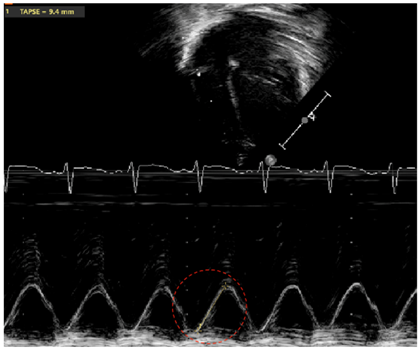

| TAPSE | Tricuspid annular plane systolic excursion (TAPSE) is a marker evaluating RV systolic function using the M-Mode tracking motion of the tricuspid valve (line of interrogation crossing the apex and attachment of the tricuspid valve to the RV-free wall). It estimates the longitudinal displacement of the tricuspid valve from peak diastole to peak systole. Low values (by age) indicate RV dysfunction [32,33,34]. |

| TAPSE—tricuspid annular plane systolic execution | ![]() |

| Legend: Marker of longitudinal systolic function of the right ventricle (RV) (which primarily contracts longitudinally). The M(motion)-Mode is used with the line of interrogation passing through the attachment of the tricuspid valve at the level of the free wall of the RV, and through the RV apex. The distance travelled from end-diastole to peak of systole is measured by following the line of the attachment of the tricuspid valve on the M-Mode tracing through time (red circle). Occasionally, superimposed tissue Doppler allows to follow the period of systole with increased precision. Z-scores have been published by gestational age/postmenstrual age, as well as chronological age for term infants [34,56]. | |